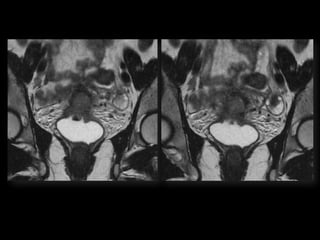

Dr. Hedvig Hricak

HISTORY

•   42 yo female

•   Recent immigrant from China

•   C/O postcoital and intermenstrual bleeding

•   Abnormal GYN exam

•   Abnormal biopsy

•   Further imaging performed

• What is the diagnosis?

• Staging?